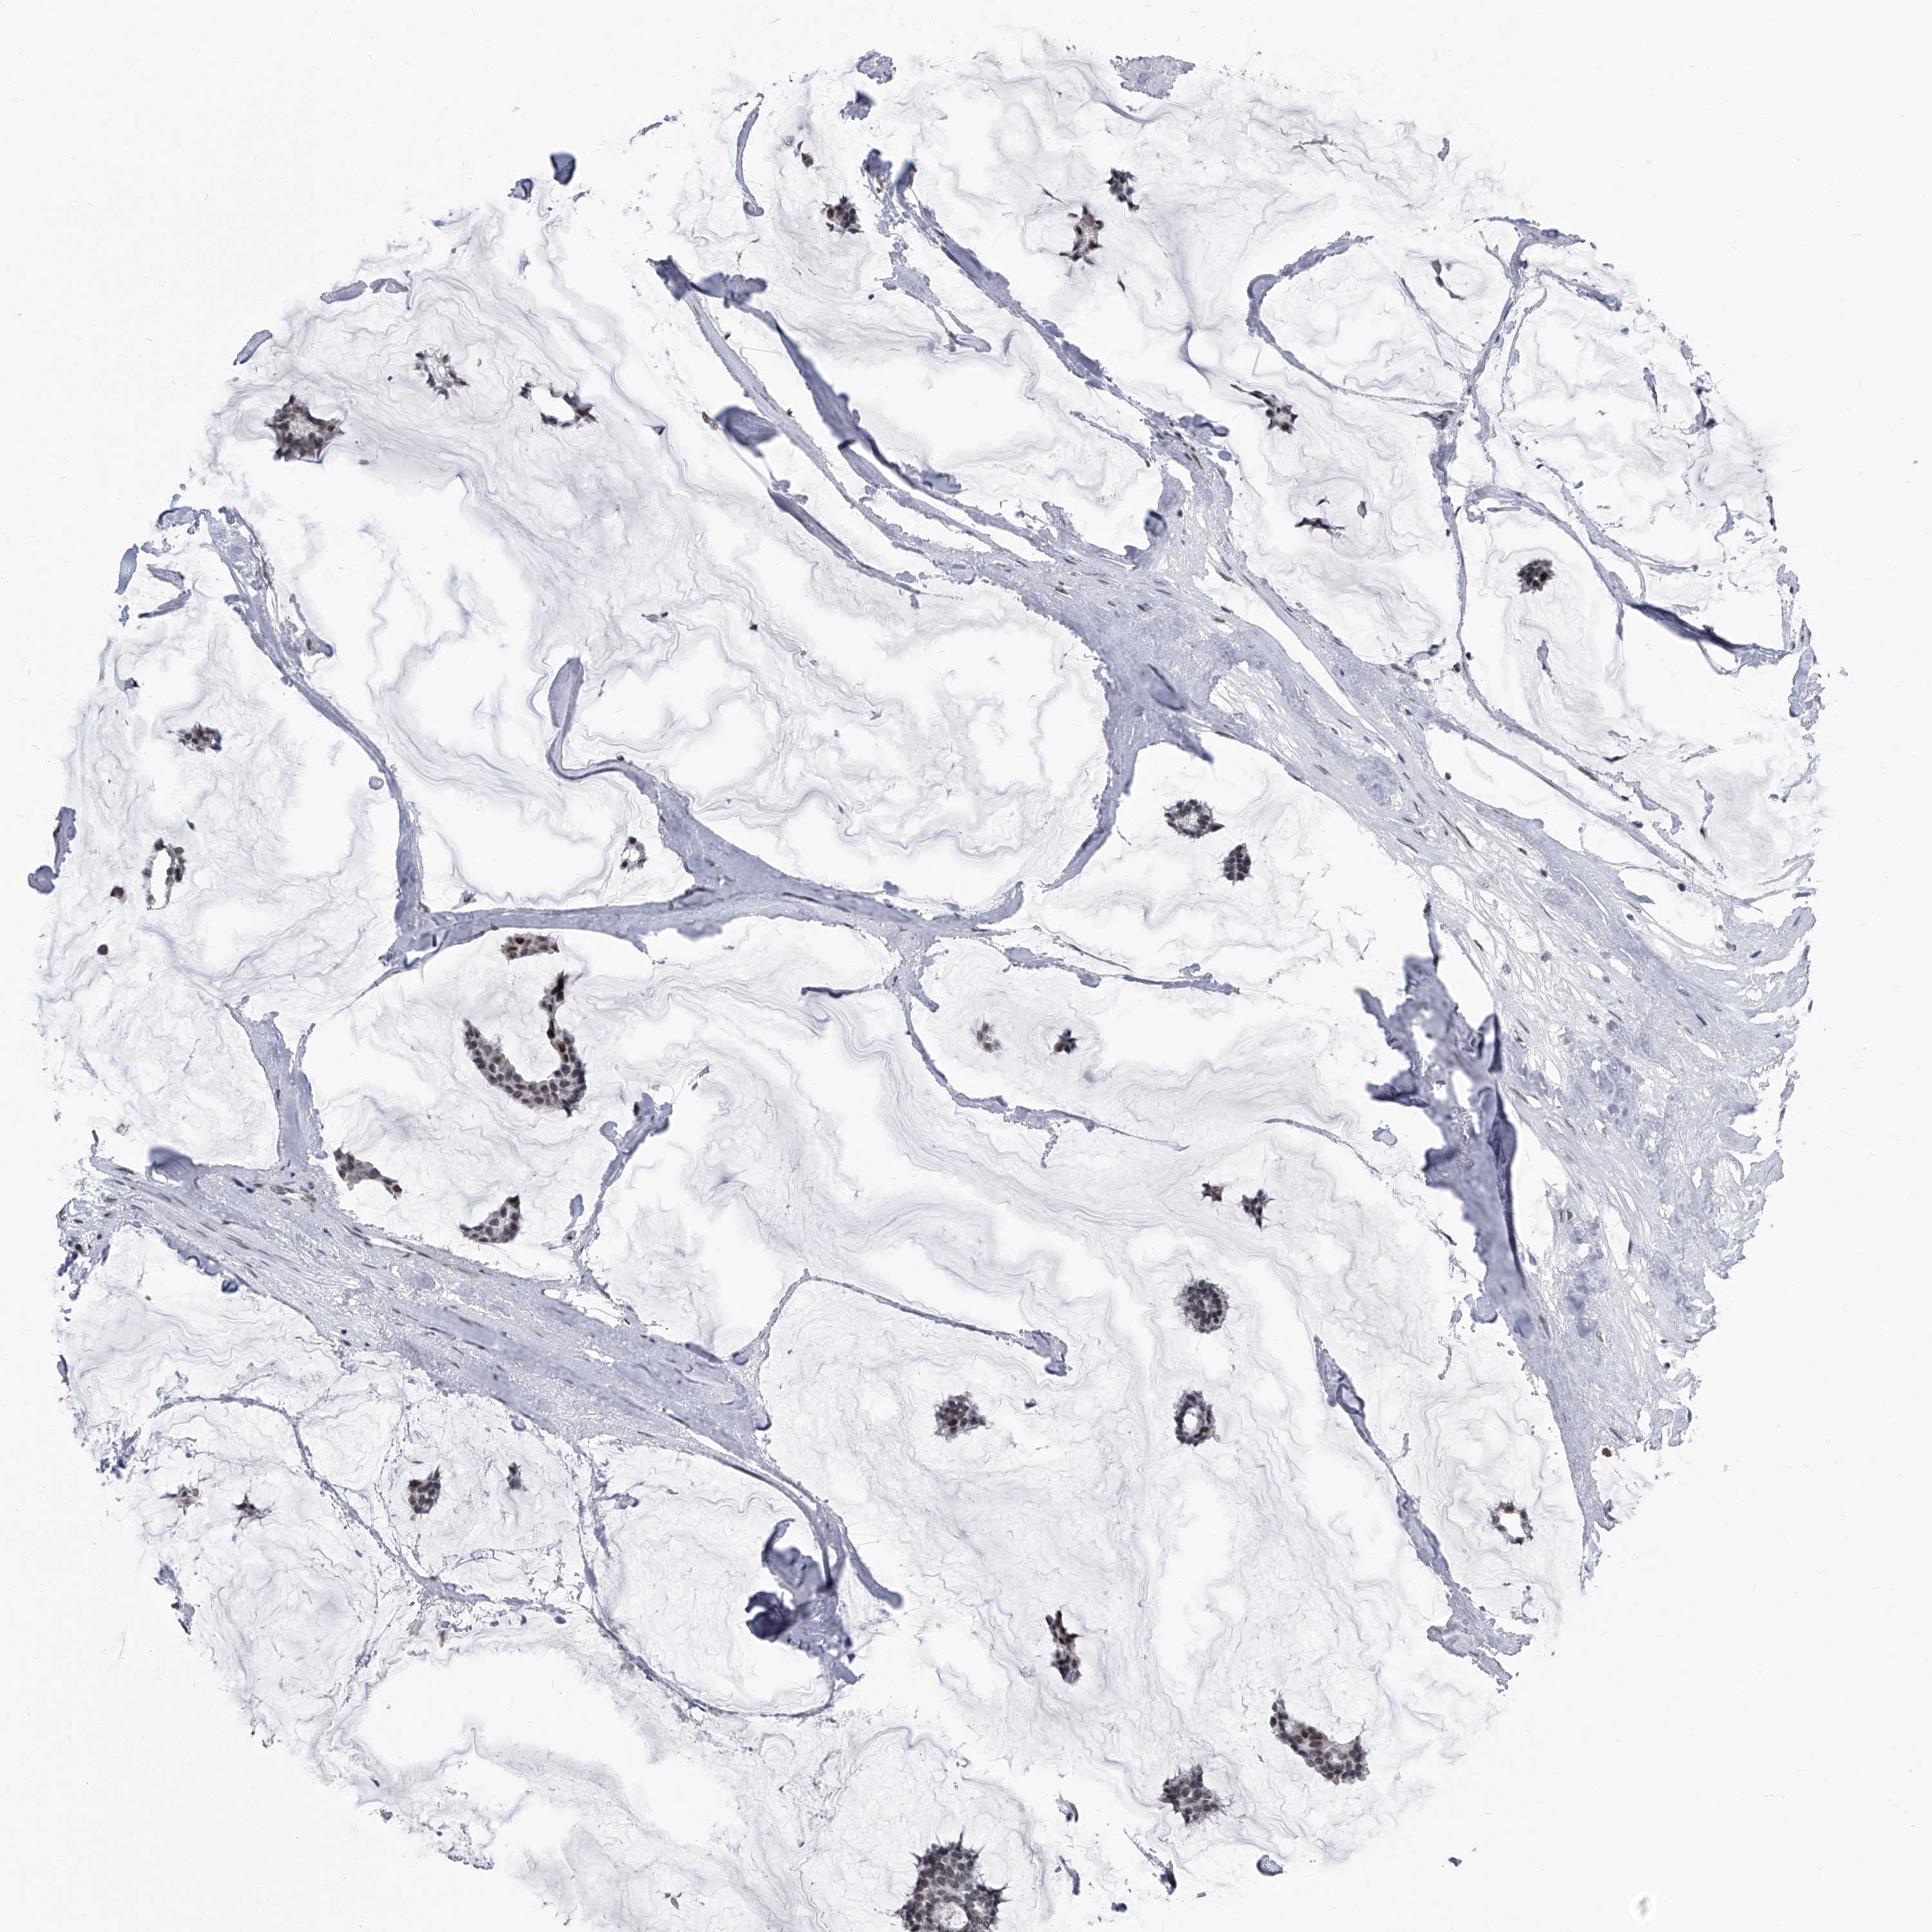

BRCA TCGA BRCA VALIDATION PROTEIN EXPRESSION

ANTIBODIES

AND

VALIDATION